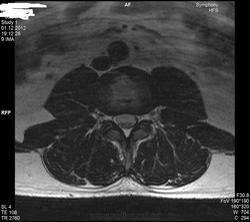

Уважаемые специалисты. МРТ после операции 8 нед.

Операция геминоламинэктомия L4-5 с установкой системы динамической стабилизации между остистыми 4-5.

После операции боли в пояснице прошли, боль в коленях и голенях осталась в неизменном виде. Ниже верхней трети голени боль не опускается.

По задней стороне туловища в ногах болей никогда не было. Уважаемый специалист, к сожалению не рентгенолог, утверждает что нет никаких признаков радикулопатии. Не посмотрите своим профессиональным взглядом.